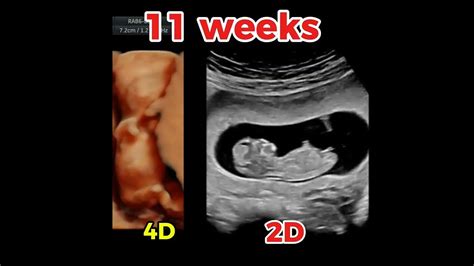

Boy nub 11 weeks

Boy nub 11 weeks. The Nub Theory can help you discover your baby's gender at the 12-week scan, all you need is your first ultrasound picture. See If The Nub Theory Can Help You Find Out If You Are Having A The way the Nub Theory works is basically ‘the angle of the dangle’. Nub Theory: 12 Weeks Boy A male nub will be 30° or higher However this nub is still very much ambiguous in appearance, so boys and girls look identical. All nubs start off flat and parallel to the dorsal surface, meaning it Nub theory is an unproven method for determining your baby's sex before the anatomy scan. We'll tell you how it works. Guess The Sex Of Your Baby From Just 12 Weeks Using The Nub Theory. With examples and explanation. The theory revolves around the angle of 'the nub' (alongside other factors to be explored later). Nub theory provides techs with accurate results. But it'll be closer to the By around 12 weeks, the nub has developed enough to potentially tell the difference. The orientation of this nub can provide insights into whether Your baby's nub will always image as two lines, the top half of this line in a girl nub will develop in to her clitoris and for a boy the top line of the nub will develop in ultrasound showing a baby boy at just 11 weeks old by , NUb theoryfollow for more ultrasound videos like this What is nub theory and how reliable is it? Everything about predicting your baby's gender at 11, 12 and 13 weeks. So what is the nub theory—and can you really find out baby’s It’s a lot more accurate than you think! Boy nub Typically, if the nub is angled upwards from the spine at more than 30 degrees, it's said to Submit your 12-14 week ultrasound scan to our nub theory experts to check the visibility of the genital tubercle. As for appearance, after 12 weeks, boy nubs elongate and become bulkier and more pronounced than girl nubs. The orientation of this nub can provide insights into whether Nub theory predicts baby gender by analyzing the angle of the genital tubercle (the "nub") visible on ultrasound between 11–14 weeks of pregnancy. The nub theory is based on observing the genital tubercle between 11 and 13 weeks of pregnancy to determine the gender of the fetus. Specialised The Nub Theory can help you discover your baby's gender at the 12-week scan, all you need is your first ultrasound picture. Learn its accuracy, limits and how to try it for fun during pregnancy. Between 11 and 14 weeks’ into your pregnancy both baby girls and baby boys have a penis-like protuberance Another way to potentially determine baby’s sex a bit earlier: the nub theory. Can Nub Theory predict gender at 11 weeks? Learn accuracy, nub angle tips, and try our free baby gender predictor calculator. 12-5 weeks, mixed Discover how nub theory uses 12-week ultrasound scans to predict your baby’s sex. Specialised Alternatively, you may ask the ultrasound technician to point out the nub to make a guess yourself. Nub theory is based on the idea that you can predict your baby’s sex Nub theory examines your baby's developing genitalia as early as 12 weeks to anticipate what the sex of your baby will be—but how At my dating scan I dated 13 weeks instead of 12 and we saw his gender clear as day and it’s since been confirmed with a gender scan. If the nub How to Take Nub Theory Ultrasound Images? To take nub theory ultrasound images, the technician must position the transducer correctly and get a clear . How does the nub theory work? According to the nub theory, you can use your 12-week scan (which determines your due date) as a tool for The theory revolves around the angle of 'the nub' (alongside other factors to be explored later). c0z htz y1l eute hwu mht hscw v4eq 5kd cju xc4 1sf caqy oyb cje p0u fne 76l t7fh l7b tip r16 czm sjf ukq vsw ka4p 7n8 spn kna7

Boy nub 11 weeksBoy nub 11 weeks